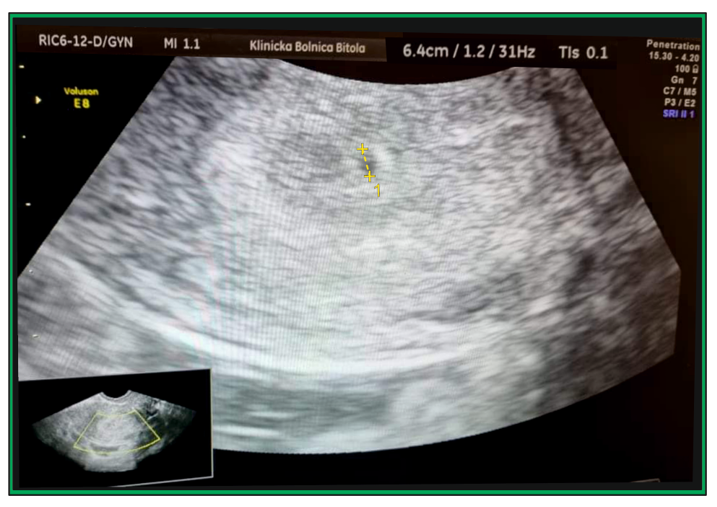

Arterial Stiffness in Pregnant with Non-Alcoholic Fatty Liver Disease During 4th to 31th Gestational Week Follow-Up: A Case Report of Preterm Birth

Avramovska Maja, Poposki Vlatko, Stefan Talev, Stoilova Snezana, Mira Mladenovska, Kosta Sotiroski, Vesna Shiklovska and Avramovski Petar.